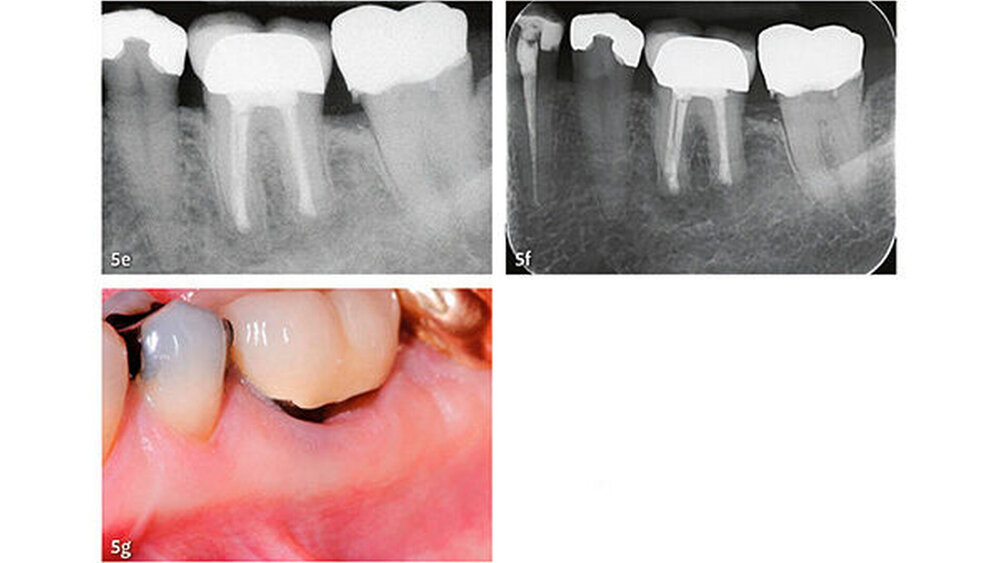

Klinische Studien

Die wesentlichen Daten von klinischen Studien über die Anwendung von MTA als retrogradem Füllmaterial sind in Tabelle III zusammengefasst. Die erste klinische Studie mit Auswertung der Erfolgsrate nach MTA-Anwendung in der apikalen Chirurgie wurde von Chong et al. (2003) publiziert - es war auch gleich die erste randomisierte Studie, welche MTA mit einem anderen retrograden Verschlusszement untersucht hat. Generell zeigen alle klinischen Studien sehr hohe Erfolgsraten für MTA in der apikalen Chirurgie (83,7% bis 96%). Die von uns 2014 publizierten Langzeitdaten (5 Jahre Beobachtungsdauer für alle behandelten Zähne) mit einer Erfolgsrate von 92,5% deuten auf eine sehr gute Stabilität und auf ein hohes Abdichtungsvermögen von MTA (von Arx et al. 2014) (Abb. 4 und 5).

Die Dokumentation der 10-Jahresdaten ist im Gange, und die bisherige Analyse deutet auf eine konstant hohe Erfolgsrate auch nach zehn Jahren (Abb. 6). Eine systematische Auswertung mit Meta-Analyse aller bis 2007 publizierten retrograden Füllmaterialien in Vergleichsstudien mit mindestens zwei getesteten Verschlussmaterialien ergab für MTA die höchste Wahrscheinlichkeit einer periapikalen Ausheilung (91,4%) (von Arx et al. 2010a).